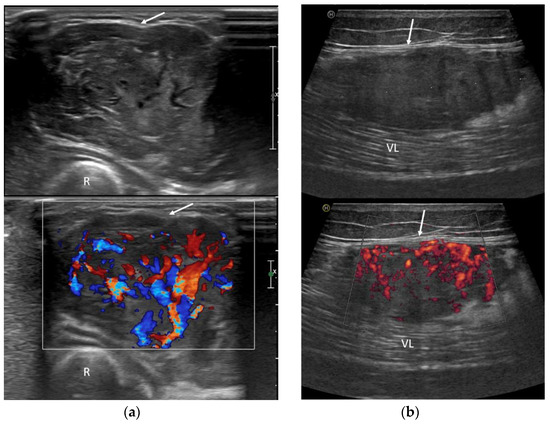

3.3. Ultrasound Features

- Inhomogeneous, mainly hypoechoic US pattern with strong internal vascularization at Color-Doppler evaluation

- Li, W.; Zhang, S.M.; Fan, W.; Li, D.; Tian, H.M.; Che, D.M.; Yu, L.M.; Gao, S.M.; Liu, Y. Sonographic imaging features of alveolar soft part sarcoma: Case series and literature review. Medicine 2022, 101, e31905. [Google Scholar] [CrossRef]

| Li, 2022, [24] | 3 | 23–30 | 81 mm | 2/3 (66.6%) | US, MRI, CT | US: Heterogeneous hypoechoic tissue. Well-defined margins. Intra- and peri-tubular vessels. Highly vascularized lesions on color-Doppler. MRI: Slightly high SI on T1w, high SI on T2w. Flow voids. CT: Slightly high density without significant bony destruction on CT. |

| Gulati, 2021, [27] | 16 | 3–72 | 83 mm | 14/16 (87.5%) | US, CT, MRI, PET | PET: SUV of >2.5. CT: Intense CE. MRI: Slightly high SI on T1w, high SI on T2w. Flow voids. Intense CE. US: Circumscribed lobulated homogeneously hypoechoic pattern. Multiple enlarged feeding vessels. |